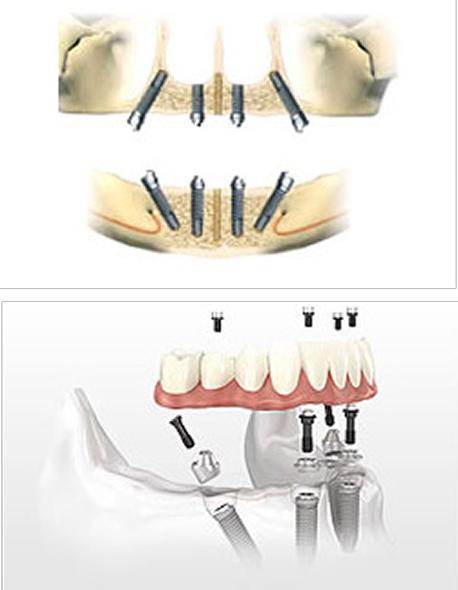

歯がなくても1日で噛めるようになるインプラント治療

~オールオン4・オールオン6~

新しいインプラント治療では、歯を全て失っている方も、4本(場合により6本)のインプラントで12本分の咬合を支える植立が可能です。治療期間を短縮し、手術後すぐに固定式の歯が入り、入れ歯から解放される点が魅力です。

一方、上顎など骨質が柔らかい部位では、安定性を高めるため本数を増やす(6本程度)ことがあります。また、仮歯をすぐにはめず治療期間を長く取る選択肢もあり、部位の骨質に合わせた治療計画を提案します。

メリット

- 手術当日に仮歯を装着するため、その日のうちに審美性と基本的な咀嚼機能が回復します

- 4本または6本のインプラントで全ての歯を支えるため、従来法に比べ費用を抑えることが可能です

デメリット

- 保険対象外となり治療費が高額になる可能性があります

- 残っている歯は抜歯が必要になることがあります

- 残高度な技術を要するため、対応できる医療機関は限られます

- 残骨量が著しく不足している場合、骨造成などの追加手術が必要になることがあります